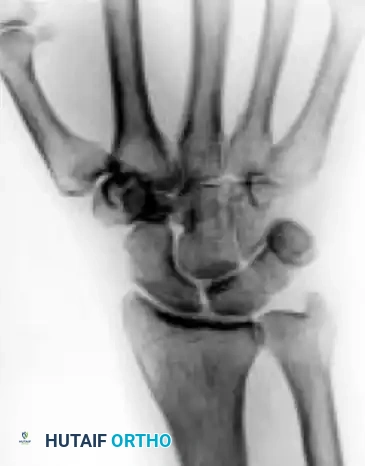

Stage IIIB

- Description: Lunate fragmentation is accompanied by fixed rotation of the scaphoid (dorsal intercalated segmental instability - DISI pattern) and proximal migration of the capitate.

- Treatment: Proximal row carpectomy (PRC) or STT fusion. The internal collapse pattern must be addressed.

When the lunate has collapsed, the scaphoid has rotated (DISI), or secondary arthritis has set in, joint leveling and revascularization are no longer viable.

- Proximal Row Carpectomy (PRC): Excision of the scaphoid, lunate, and triquetrum. Converts the wrist to a simple hinge joint between the capitate and the lunate fossa of the radius. Requires a pristine capitate head.

- Scaphoid-Trapezium-Trapezoid (STT) Fusion: Halts the DISI collapse pattern and unloads the lunate by transferring forces through the scaphoid.